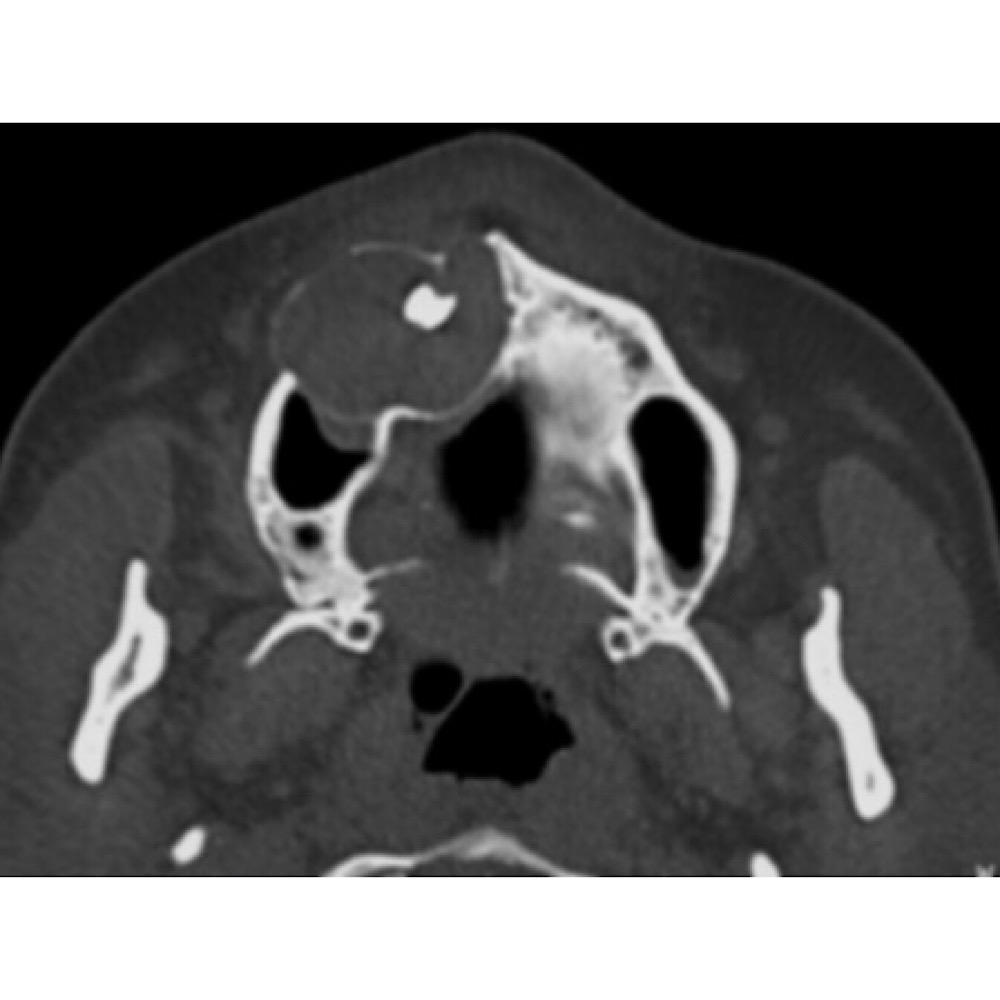

<br />The ameloblastoma is the most common clinically significant and potentially lethal odontogenic tumor. Excluding odontomas, its incidence equals or exceeds the combined total of all other odontogenic tumors. May arise from:<br /> 1. Rests of the dental lamina,<br />2. A developing enamel organ,<br />3. The epithelial lining of an odontogenic cyst,<br />4. The basal cells of the oral mucosa.<br /> Three different variants, each with specific implications for treatment and a unique prognosis: solid or multicystic, unicystic, and peripheral. The solid and multicystic forms of the tumor do not produce an effective connective tissue capsule or evoke an encapsulating mechanism by surrounding bone or soft tissue The unicystic ameloblastoma, however, does have a peripheral connective tissue wall, which may be loose or dense, and relatively thin or thick<br />Treatment:<br />The treatment is surgical resection with a safety margin. A safe margin of uninvolved bone is<br /> approximately 1.5 to 2 cm for solid and multicystic lesions, and 1 to 1.5 cm for unicystic and peripheral lesions. Post-treatment patients should be followed for 15 to 20 years or longer due to high recurrence rate and slowly growing behavior of tumor.<br /> Immediate reconstruction can be performed if there is surgical, specimen radiographic, or intraoperative frozen section certainty of complete excision of the tumor. However, if there is uncertainty about the resection margins, reconstruction should be delayed until permanent tissue sections are studied. Maxillary lesions must be resected aggressively because of the ease with which the tumor can spread through the less dense cancellous and cortical bone, with access to the pterygoid region, sinuses, infratemporal space, and skull base.<br /> <br /> Although some studies suggest that the ameloblastoma may be radiosensitive, radiation therapy has seldom been used as a treatment modality because of the intraosseous location of the tumor and the potential for secondary radiation-induced malignancy developing in a relatively young patient population.